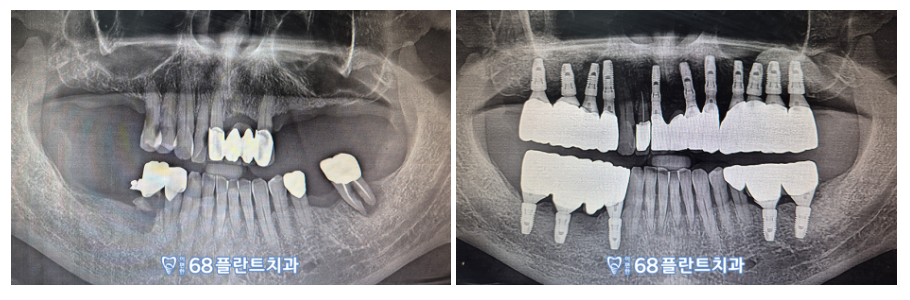

◆ 전 > 후 ◆

(2023.06.15ㅡ>2024.01.09)

이렇게 전 / 후 파노라마 사진을 통해

상실된 부위가 회복된 것을

확연히 보실 수 있습니다.

환.자분께서 이제 어금니로

마음껏 식사 하실 수 있겠다며

이편한68플란트치과를 찾아오길 잘했다며

감사의 인사를 전해주셨답니다.